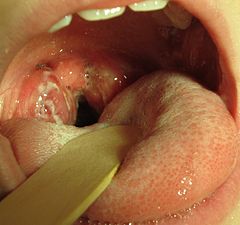

The person receiving the throat culture is asked to tilt his or her head back and open his or her mouth. The health professional will press the tongue down with a tongue depressor and examine the mouth and throat. A clean swab will be rubbed over the back of the throat, around the tonsils, and over any red areas or sores to collect a sample.